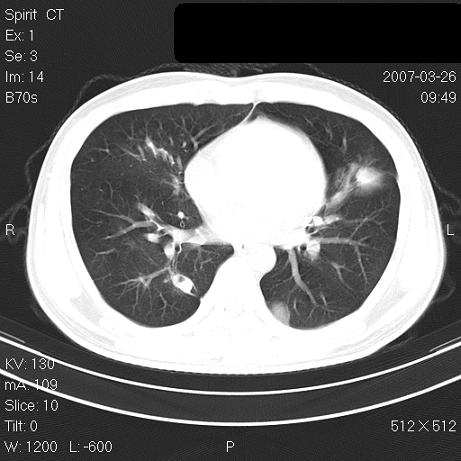

标题: CT7171B:补充治疗后2周复查

治疗后2周复查,请讨论

结合以前的ct片,还是考虑肺挫伤,吸收多了。

支持:创伤性湿肺。现肺挫裂伤(出血 积气)大部分吸收。建议继续治疗!

支持:创伤性湿肺、肺挫裂伤。现肺挫裂伤(出血、渗出、液气腔)大部分吸收。建议继续治疗!

经治疗后病灶明显吸收,考虑创伤性湿肺、肺挫裂伤